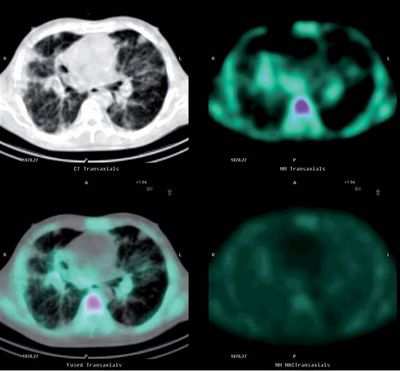

Ученые разработали новый агент для визуализации рака, который ищет интегрин в организме и прикрепляется к нему. Биохимически интегрин способствует передаче клеточных сигналов, что делает его идеальным для визуализации растущих и метастатических опухолей, которые распространились через кровь или лимфу и поселились в других органах. …